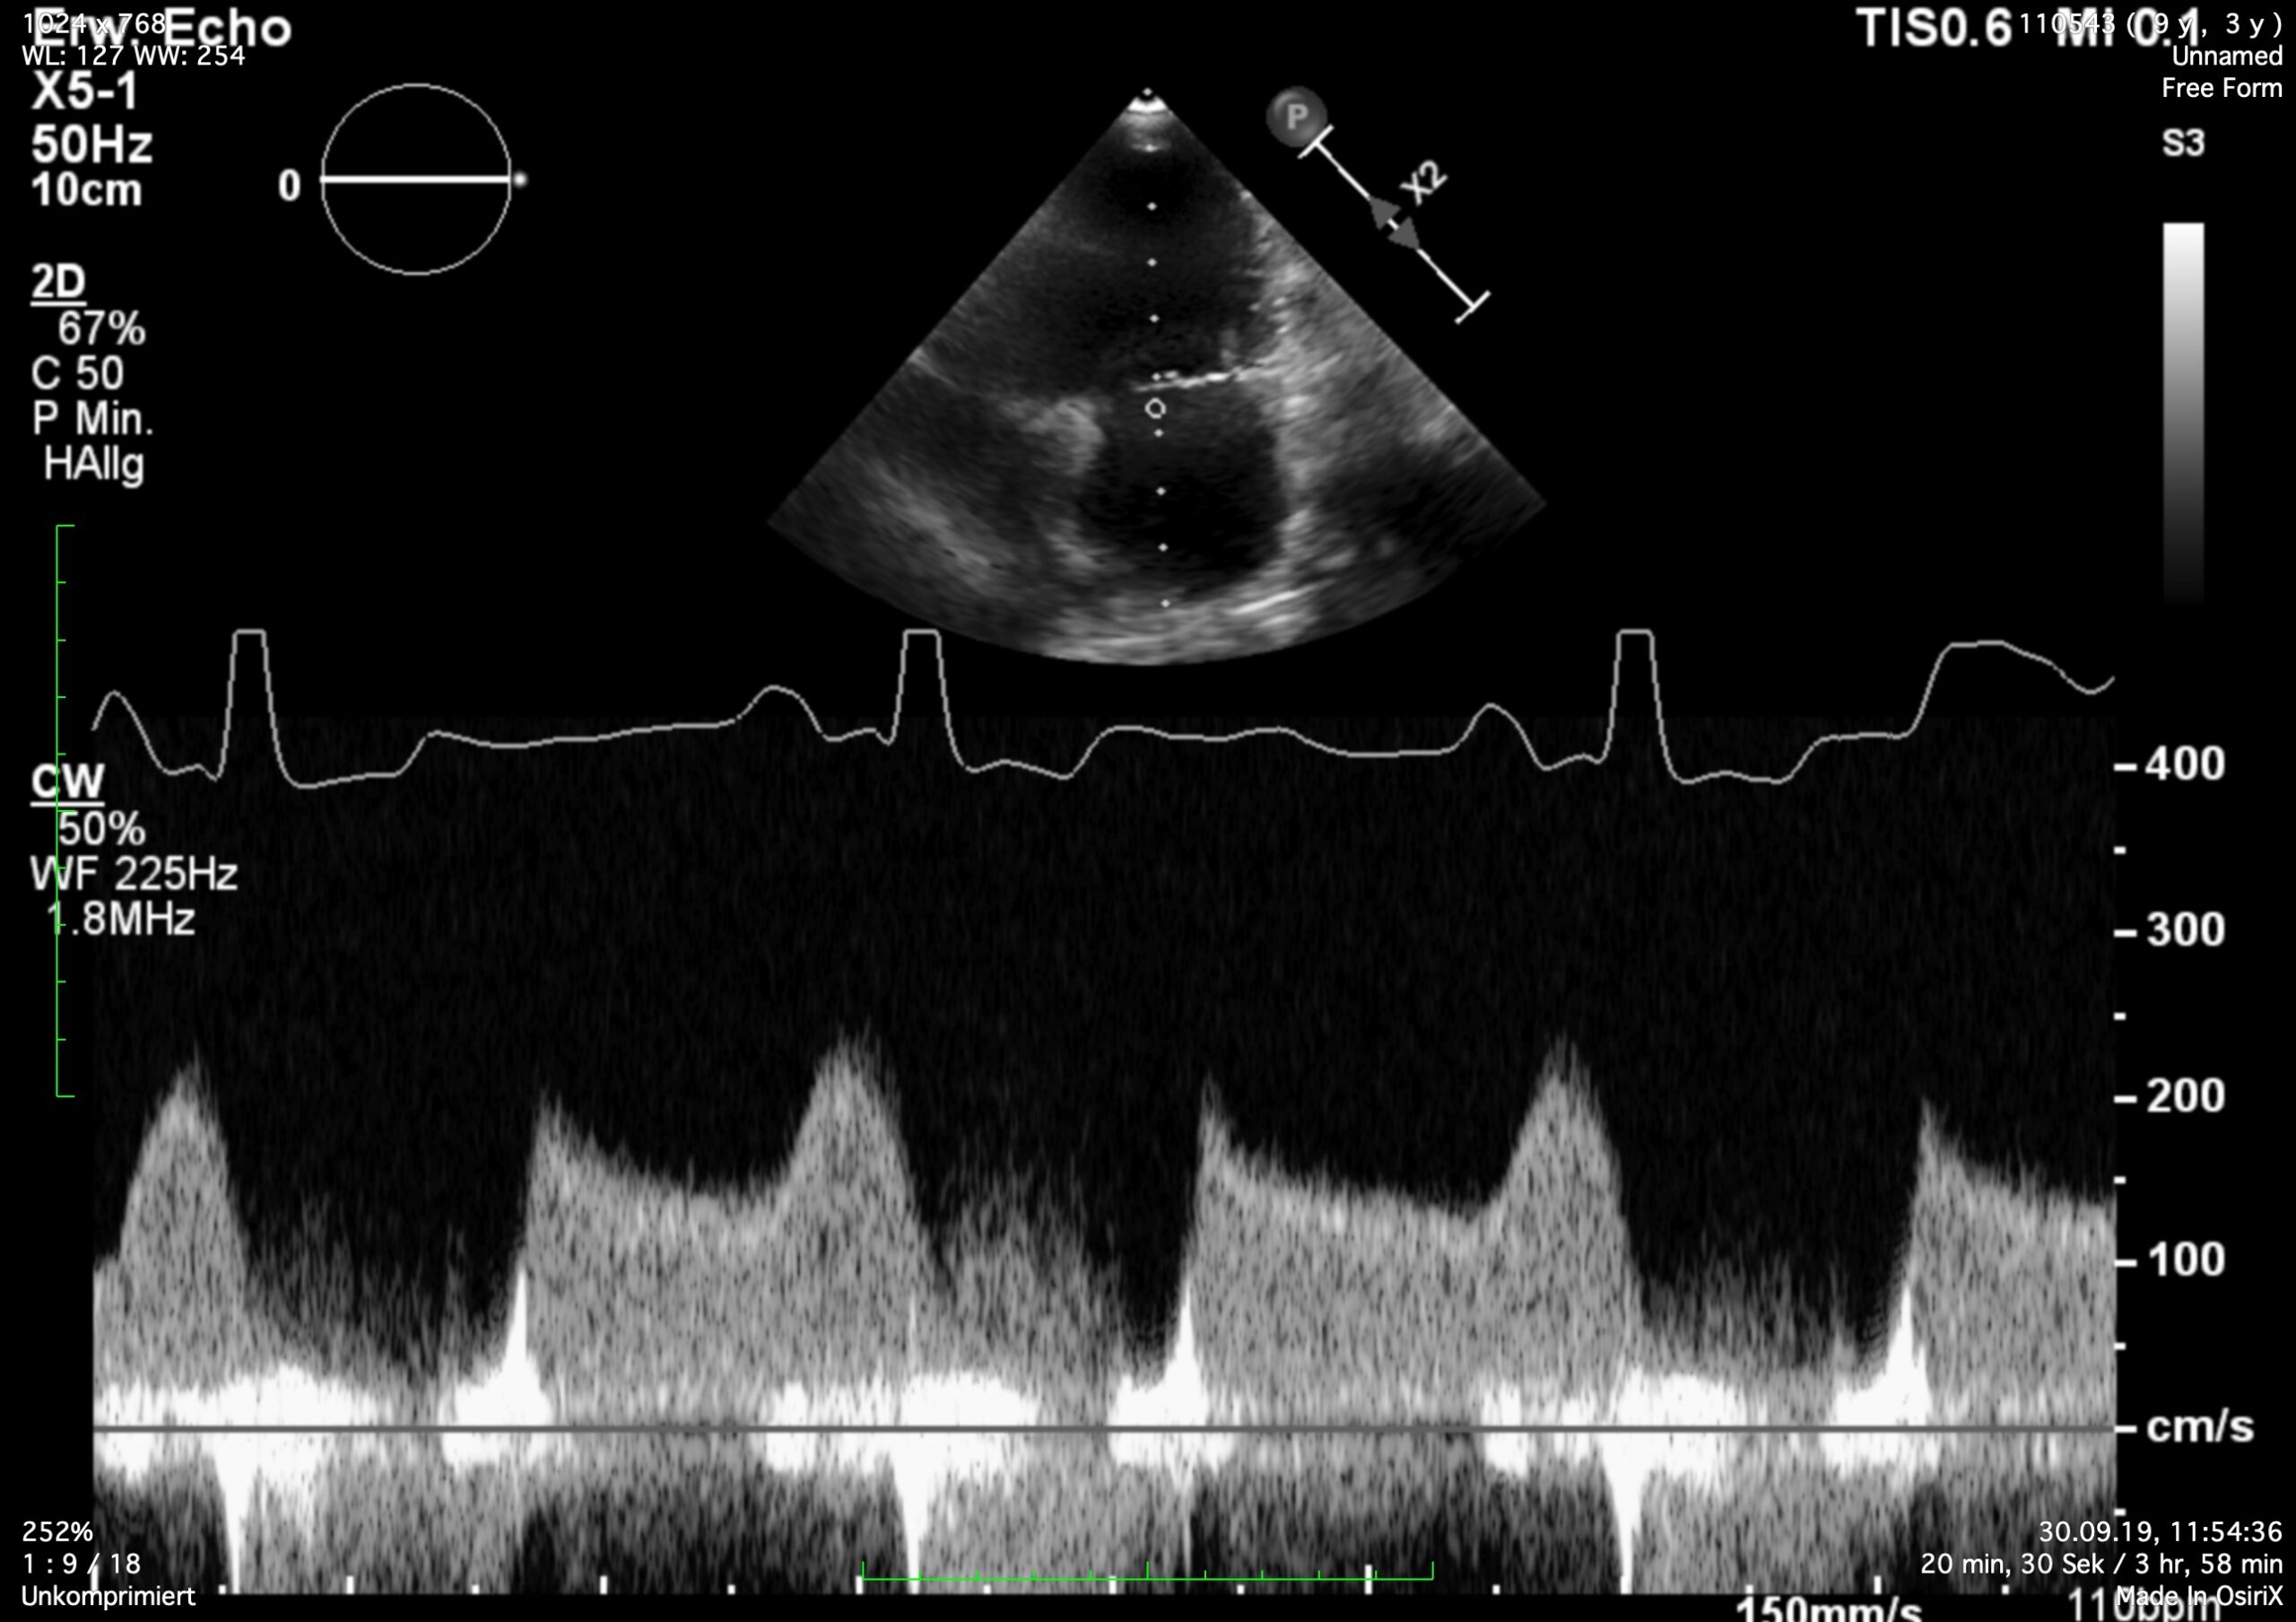

I see MS at all ages, because it is frequently missed in young dogs. But this case is not a MS. It is diagnosed as a combination of 2D-echo findings and the typical Minflow profile (E-wave very high frequently >2 m/s) confluent with A-wave. See image and video.